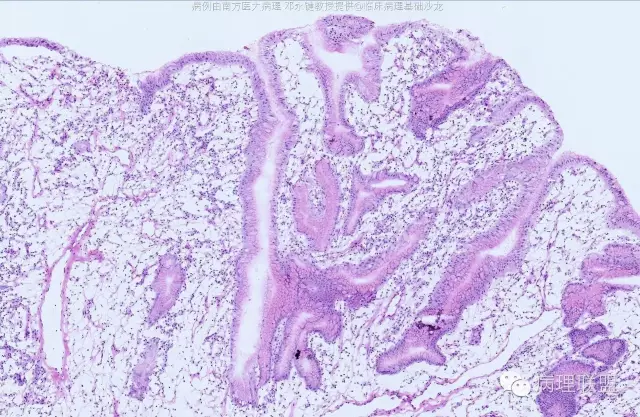

男,58岁,胃窦2.5×2.1×1.5cm大小肿物。冰冻切片。(病例由南方医科大学 邓永键教授提供,致谢!)

平滑肌束进入病变中,重点是表面腺体与正常腺体类似。

错构瘤性息肉/Peutz-Jephers息肉,在胃体,表面腺体是胃体腺,胃窦部是粘液腺;在小肠、大肠,表面腺腺体是小肠腺、大肠腺。该病变可以从食管至肛门都可发生。如果不出现出血、溃疡、梗阻症状,不体检,病人不会出现症状,不易被发现。小肠发生,易致肠梗阻、肠扭转。肛门发生,可脱出似内痔。